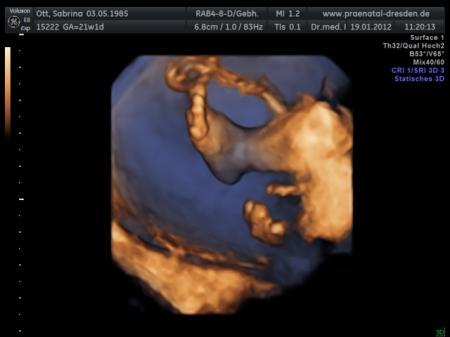

so und hier noch die kleinen Füßchen :-) wie hat der Arzt gesagt Schuhgröße 3,5 cm :-)

Bild zu

PS: Unser Kleiner hatte übrigens letzte Woche Donnerstag eine Schuhgröße von 3,01 cm *so süß die kleinen Füßchen*